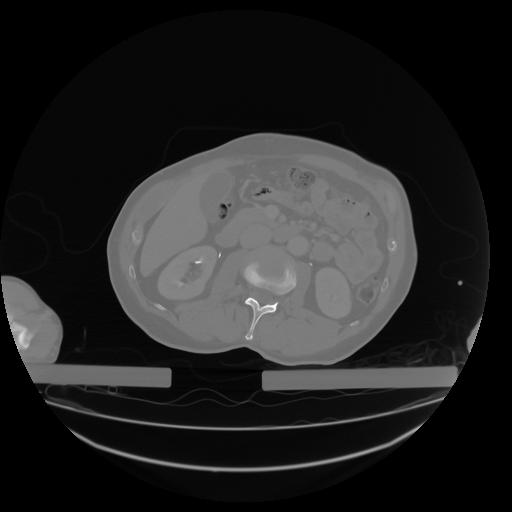

27 CUERPO,CE,Axial,3.0,CUERPO,,